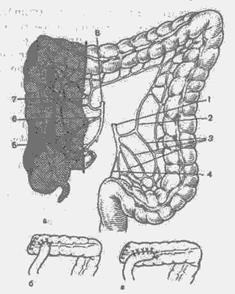

Ebben a műveletben, eltávolítjuk az egész jobb felét a vastagbél, befogják 10-15 cm-es szegmensét ileum végét, egy vak, felszálló vastagbél, a jobb oldali kanyar és jobb harmada a haránt vastagbélben (ábra. 11 a). Kerekítés a műveletet overlay sár-otransverzoanastomoza (ábra. 11, b, c).

Ábra. 11. Jobb oldali hemicolectomy (rendszer).

és - eltávolítását a határ b, c - ileotransverzoanastomozov típusok: 1 - alsó bryzheech Nye artéria; 2 - bal mintegy-zling artéria; 3 - szigmoid artéria; 4 - a felső pryamokischechnaya artéria; 5 - csípő vastagbél Arte-dence; 6 - A megfelelő kólika artéria; 7 - átlagos obodoch Nye artéria; 8 - superior mesenterialis artéria.